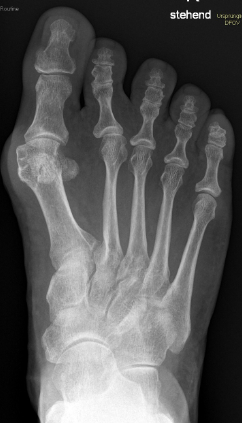

Gesamtes Spektrum der Fuß und Sprunggelenkchirurgie (Plattfuß, Spreizfuß, komplexe Vor-, Mittel- und Rückfußkorrektur, Krallenzehen und Hallux valgus/rigidus, Morton Neurinom)